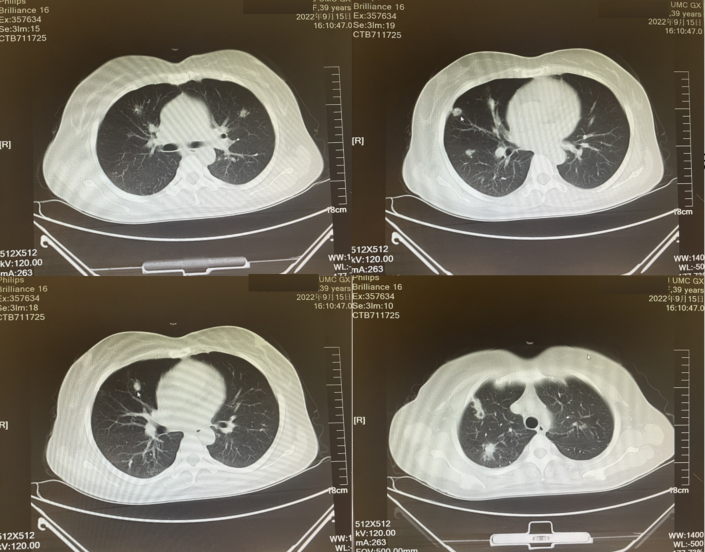

疗效评价:2022年5月、2022年7月复查胸部CT提示,肺部病灶稳定,疗效评价为SD;2022年9月复查胸部CT,较2022年7月肺部病灶稍增大,继续该治疗方案治疗。2022年12月复查胸腹部CT显示,肺部转移瘤稍增大,右半结肠切除术后,腹盆腔肠管散在扩张;进一步检查提示:平均血小板体积降低;化疗不耐受

图5 2022年9月胸部CT